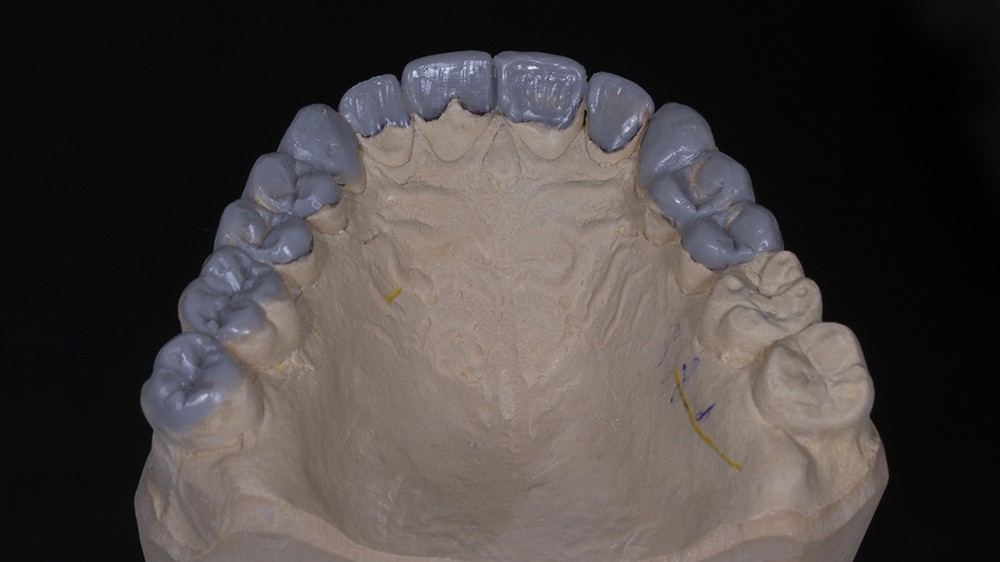

Dans un deuxième temps, un wax-up global permet de restaurer les courbes d’occlusion. Il est à noter que la présence d’égressions dentaires, faute d’antagoniste ou d’anciennes restaurations prothétiques inadaptées, crée des usures inégales au sein de la cavité buccale. Aussi, la présence de zones non recouvertes par le wax-up dans les secteurs postérieurs est courante, permettant ainsi la préservation de zones amélaires majeures pour le collage (fig. 2).